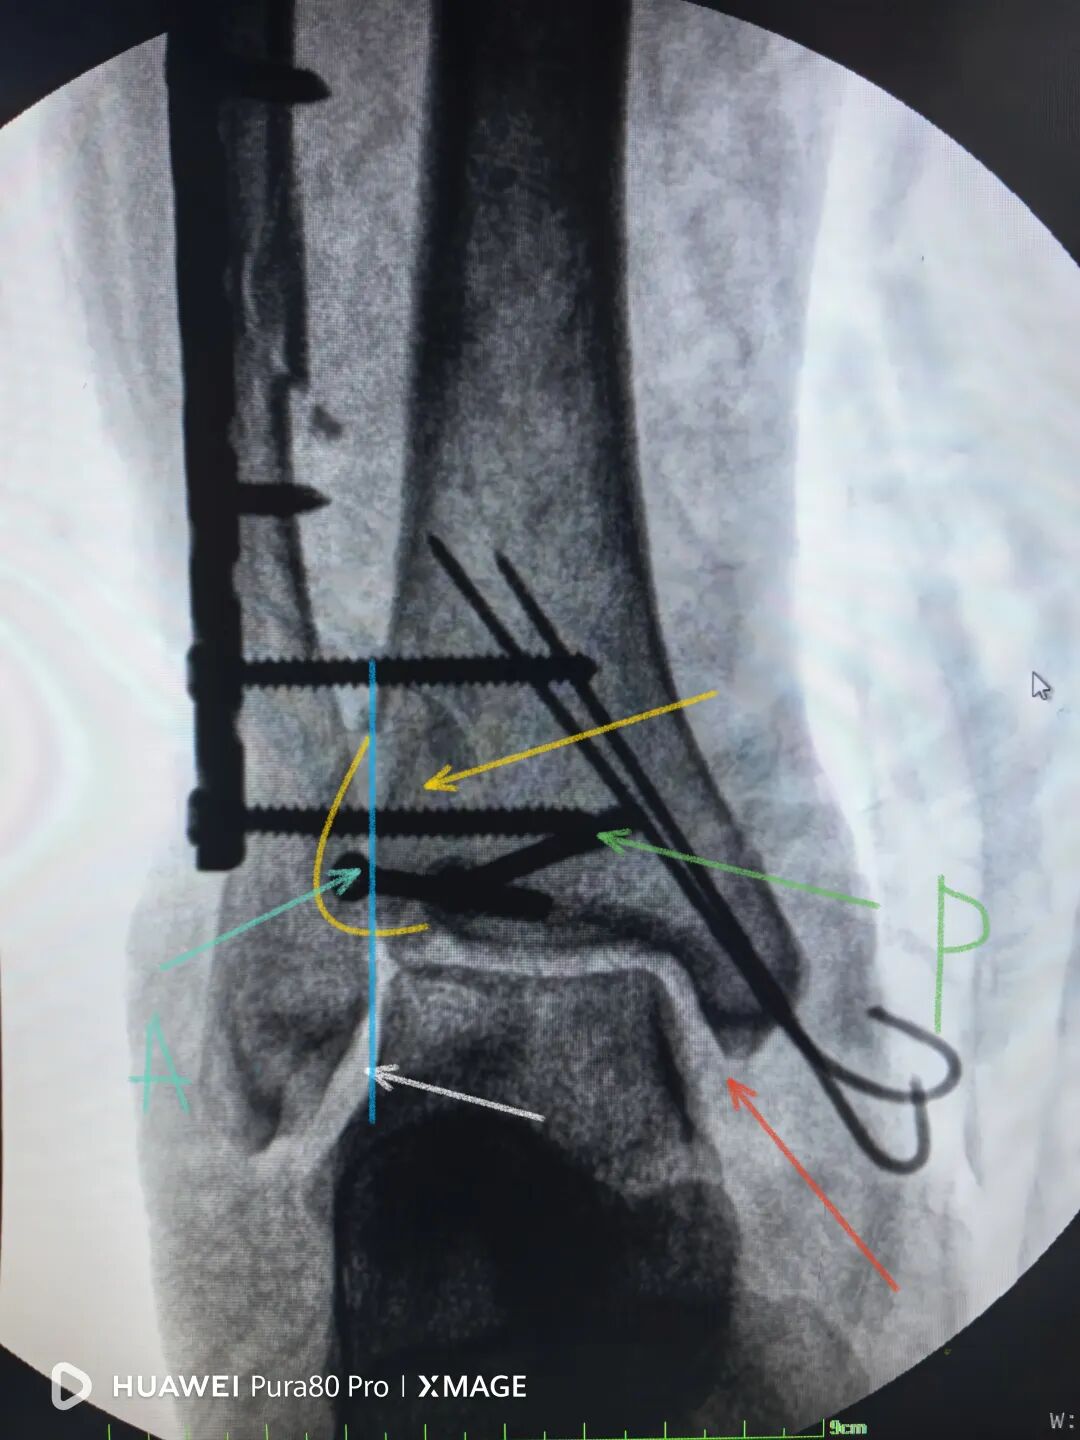

术后复查:

下胫腓关节复位良好

但前侧Chaput骨块

后侧volkmann骨块都移位